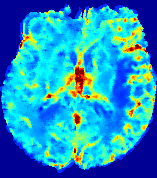

LesionRefer to captionRefer to captionRefer to captionRefer to captionRefer to captionRefer to caption𝐕rgbsubscript𝐕𝑟𝑔𝑏{\bf{V}}_{rgb}Refer to captionRefer to captionRefer to captionRefer to captionRefer to captionRefer to caption𝐕2subscriptnorm𝐕2{\|\bf{V}}\|_{2}Refer to captionRefer to captionRefer to captionRefer to captionRefer to captionRefer to captionRefer to caption3.53.53.52.82.82.82.12.12.11.41.41.40.70.70.70.00.00.0(mm/s)𝑚𝑚𝑠(mm/s)D𝐷DRefer to captionRefer to captionRefer to captionRefer to captionRefer to captionRefer to captionRefer to caption0.0200.0200.0200.0160.0160.0160.0120.0120.0120.0080.0080.0080.0040.0040.0040.0000.0000.000(mm2/s)𝑚superscript𝑚2𝑠(mm^{2}/s)Slice #1Slice #2Slice #3Slice #4Slice #5Slice #6

Figure 3: PIANO feature maps for one stroke patient, where the lesion is located in the left hemisphere. Top row: segmented stroke lesion region (white) on different slices, obtained from ISLES 2017. The corresponding slices for the PIANO feature maps are shown in the following rows.

For a better insight into an estimated velocity field 𝐕𝐕{\bf{V}} and diffusion field 𝐃𝐃{\bf{D}}, we compute the following maps: (1) 𝐕rgbsubscript𝐕𝑟𝑔𝑏{\bf{V}}_{rgb}: Color-coded orientation map of 𝐕=(Vx,Vy,Vz)T𝐕superscriptsuperscript𝑉𝑥superscript𝑉𝑦superscript𝑉𝑧𝑇{\bf{V}}=(V^{x},V^{y},V^{z})^{T}, obtained by normalizing 𝐕𝐕{\bf{V}} to unit length and mapping its 3 components to red, green, blue respectively; (2) 𝐕2subscriptnorm𝐕2\|{\bf{V}}\|_{2}: 222 norm of 𝐕𝐕{\bf{V}}; (3) D𝐷D: scalar field in Eq. 5.

Fig. 3 and Fig. 4 show the PIANO feature maps estimated from two ISLES 2017 patients: all are highly consistent with the lesion in both cases. Details of the blood flow trajectories are revealed in 𝐕rgbsubscript𝐕𝑟𝑔𝑏{\bf{V}}_{rgb} by the ridged patterns and the sharp changes of colors in the unaffected (right) hemisphere, while the flat patterns appearing within the lesion provide little directional information about the velocity and indicate low velocity magnitudes. Velocity magnitudes are more directly visualized via 𝐕2subscriptnorm𝐕2\|{\bf{V}}\|_{2}, from which one can easily locate the lesion where 𝐕2subscriptnorm𝐕2\|{\bf{V}}\|_{2} is low. D𝐷D also indicates lower diffusion values in the lesion, though with less contrast potentially due to the fact that it captures the accumulated effect of CA diffusion at the voxel-level.